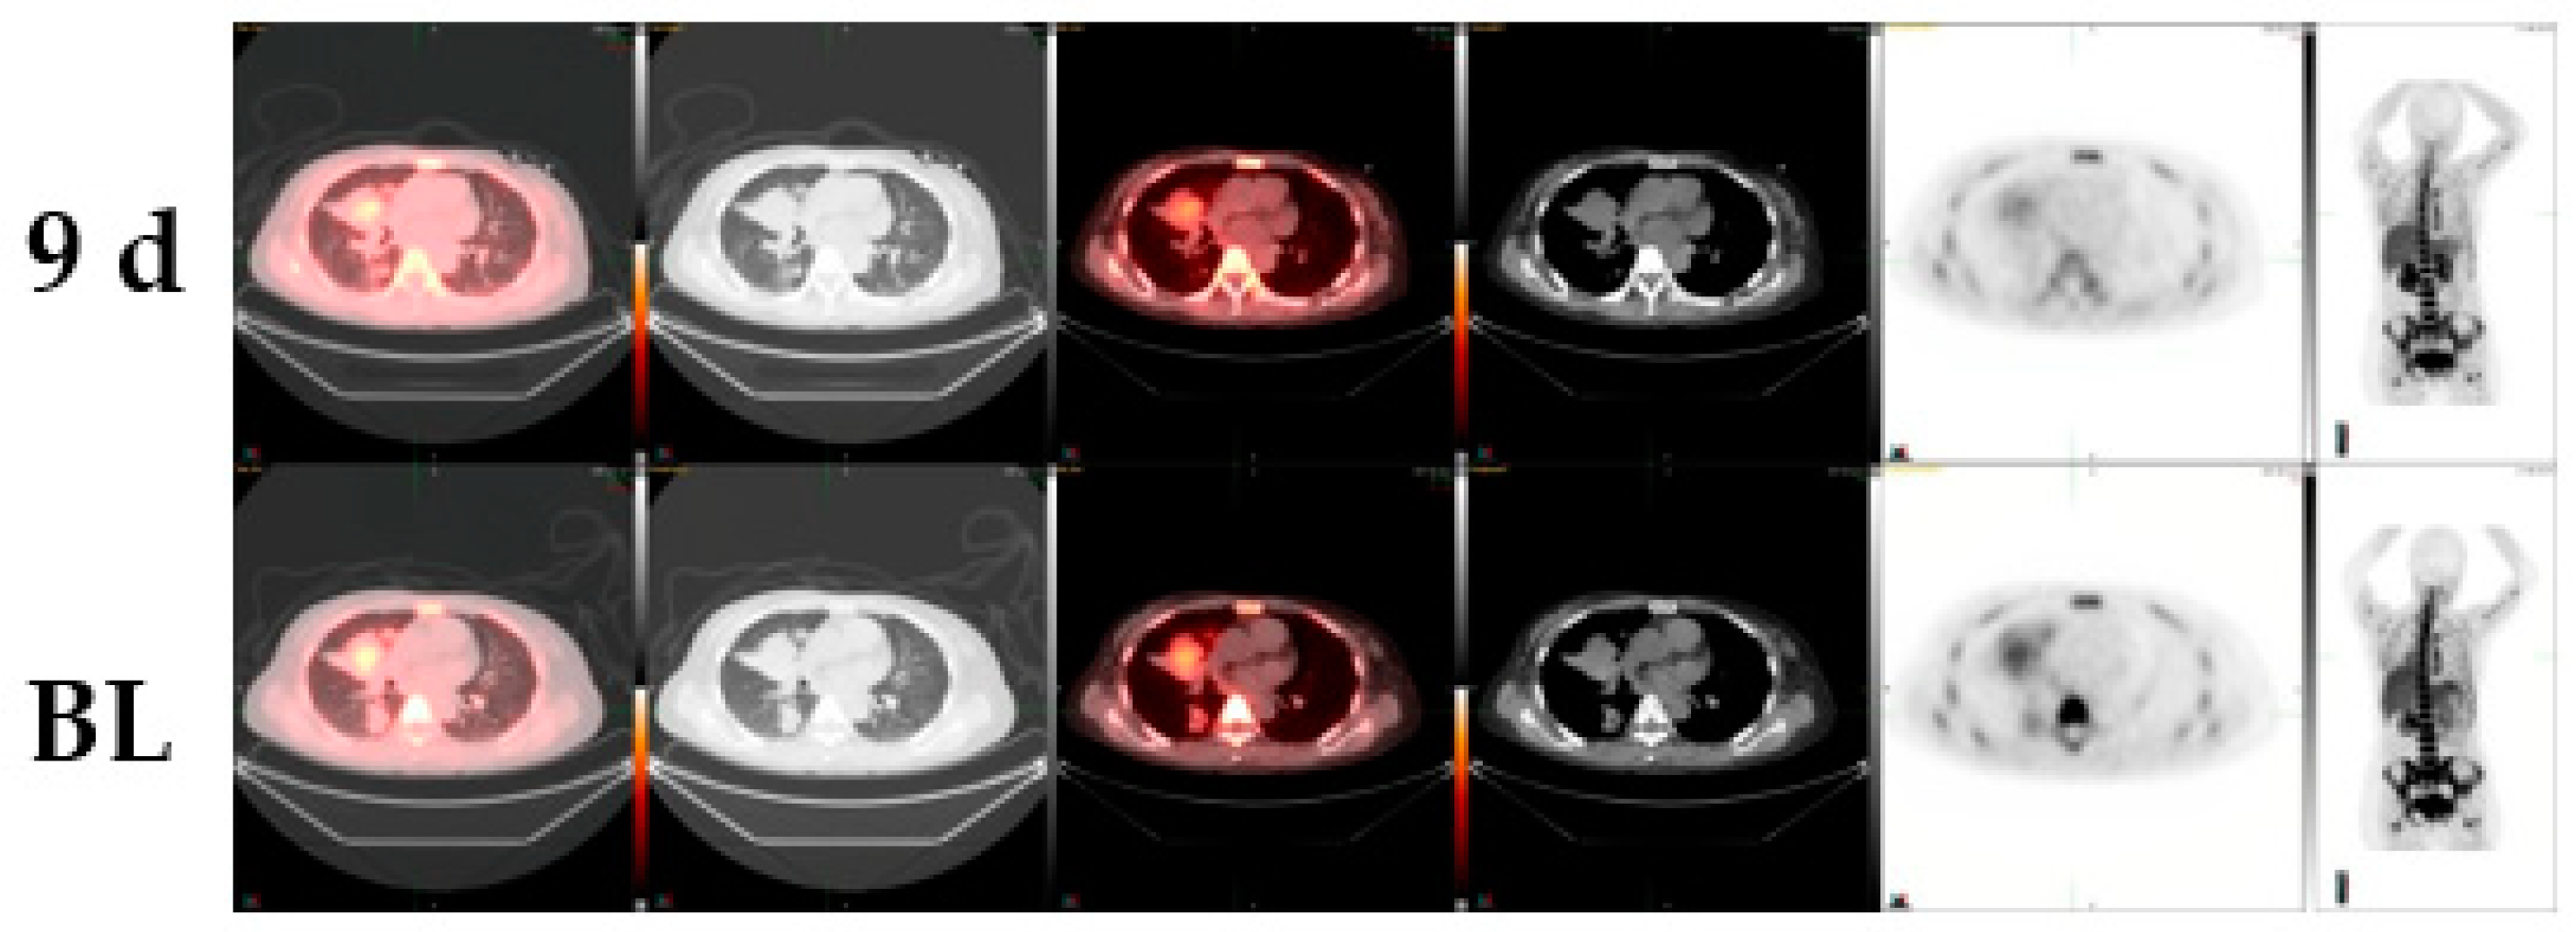

| Age/Gender/ New Therapy | Diagnosis | Previous Chemotherapy | 18F-FLT SUV Change | Comments |

|---|---|---|---|---|

| 49/male c-MET-inhibitor | small cell lung cancer | cisplatin, etoposide | −38% | FDG-change +2% CT-change 0 % |

| 51/female c-MET-inhibitor | lung adenocarcinoma | erlotinib, carboplatin, gemcitabine/docetaxel, pemetrexed, sorafenib, irinotecan, bevacizumab | −24% | EGFR positive CT-change +2% |

| 59/female MDM2 inhibitor | lung adenocarcinoma | cisplatin, vinorelbine, pemetrexed, cetuximab | −31% | EGFR negative CT-change -6% |